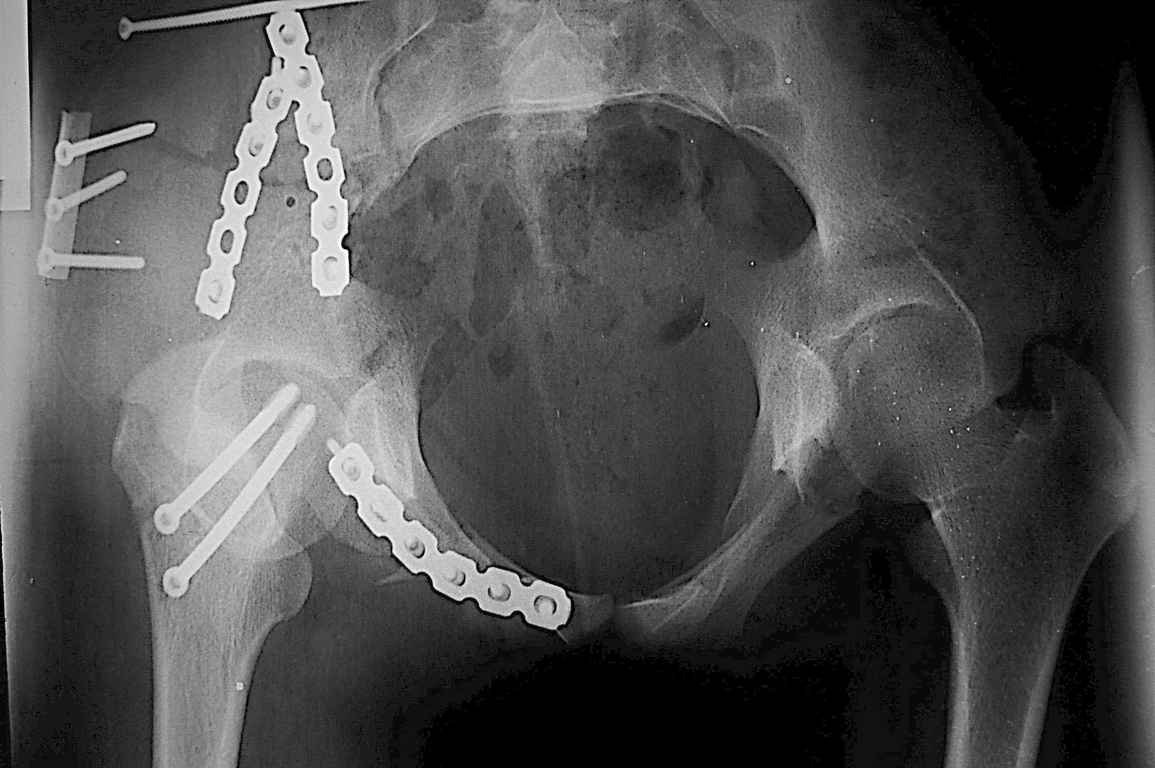

Вложение не в текстовом формате было извлечено…

Имя     : DSC_4618.jpg

Тип     : image/jpeg

Размер  : 82490 байтов

Url     : http://weborto.net:8080/pipermail/ortho/attachments/20080812/6c1c36e8/attachment-0003.jpg